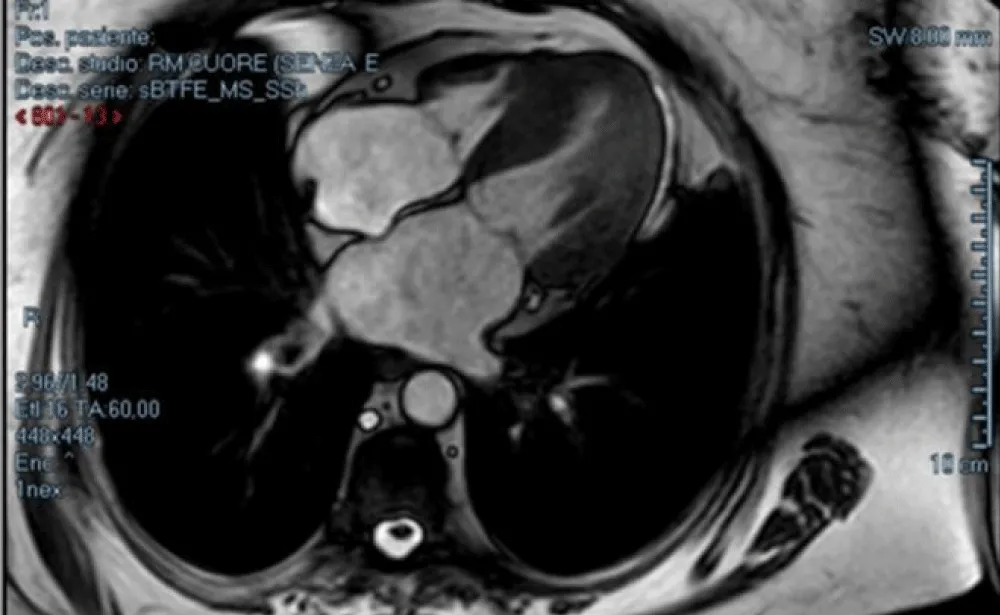

Normal myocardium has a hypointense signal, unlike the altered one which shows a hyperintense signal. The presence of Late Gadolinium Enhancement (LGE) is characteristic of fibrotic or scarred areas. In patients with AS, the LGE distribution is typically distributed in the infero-lateral wall of the myocardium, especially in the basal and middle segments (Figure 5).

Download Image

Figure 5: LGE sequences show mild hyperintensity signal in the mesocardial wall, especially along the inferolateral segment as fibrotic disarray.